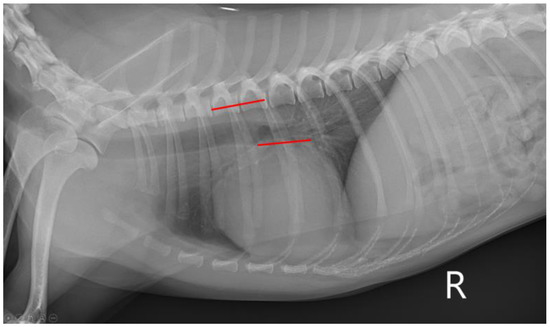

2.2. Thoracic Radiography

| VHS | 10.15 (9.60–10.50) | 10.50 (9.58–10.68) | 11.20 (10.80–12.00) | <0.001 | a,b < c α,γ,ε |